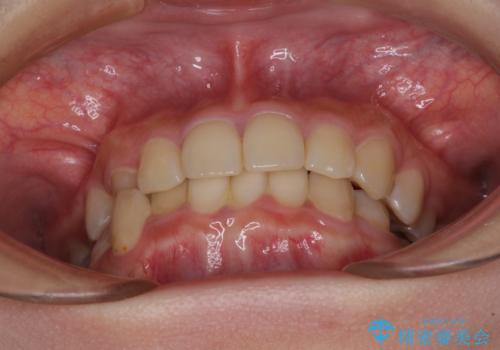

- 犬歯のクロスバイトを気にして来院された患者様です。

マウスピース矯正とワイヤー矯正の両方を提案しましたが、インビザラインの自己管理が煩わしいとのことで、ワイヤー装置による矯正治療を行うこととしました。

犬歯は歯根が太くて長いため、クロスバイトを改善するのは大変であることが多いですが、比較的スムーズに改善することができました。

インビザラインであったら、もっと期間はかかっていたような印象です。